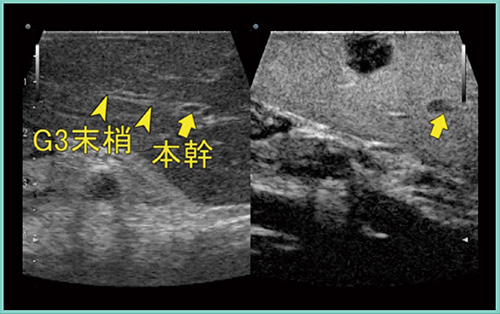

腹腔鏡手術では,造影超音波も欠かせない診断法である。造影超音波(図2)では腫瘍と本幹からグリソン鞘3(G3)末梢を確認でき,手術ではG3を温存した半球状切除をめざして,プリングル法を用いてバイポーラ鉗子によるペアン破砕法で肝離断を進めた。再度超音波検査を行うと,離断線が明瞭に描出され,G3の温存が可能と判断し,予定通りに半球状切除を行った。腹腔鏡下手術用のUST-5418は,手元の操作で探触子を4方向に向けることができ非常に視野が良いことから,手術では不可欠である。

図2 症例1:肝転移切除(S3)の造影超音波画像